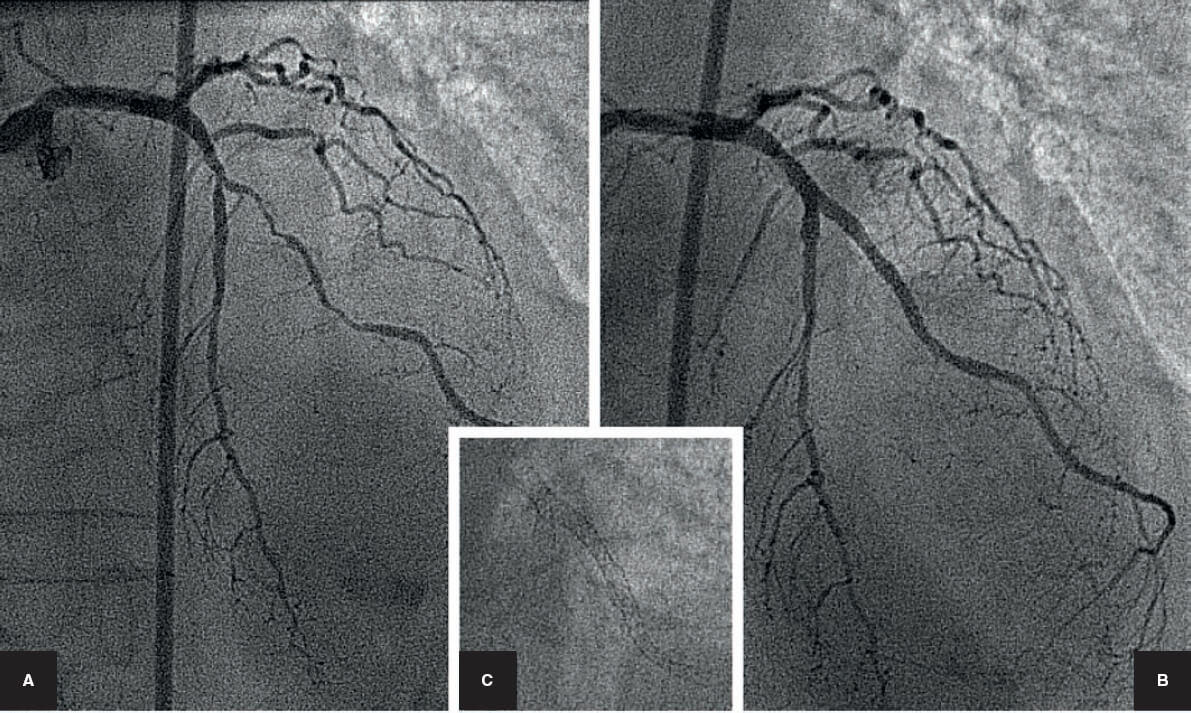

El tratamiento percutáneo de las bifurcaciones comienza en la era de la angioplastia con balón, previamente a la disponibilidad del stent coronario. Por aquel entonces ya se describían técnicas específicas, como el uso de 2 catéteres guía de 8 Fr por los que se introducían guías y balones de forma independiente en el vaso principal (VP) y en la rama lateral (RL) para realizar un inflado simultáneo (figura 1). Sin embargo, el punto de inflexión del tratamiento percutáneo de las bifurcaciones lo marcó la llegada del stent de Palmaz-Schatz. La primera técnica que se describió fue una dilatación simple con balón de la RL a través de las celdillas del stent4. A partir de entonces se describió un sinfín de técnicas para tratar ambos vasos con 1 o 2 stents. Con la llegada de los stents farmacoactivos se mejoraron los resultados de todos los procedimientos coronarios. En el campo de las bifurcaciones, se adoptó la experiencia adquirida en la época de los stents metálicos y se desarrollaron también algunas nuevas técnicas complejas: el crush y sus variantes, el TAP (T y protrusión) y el simultaneous kissing stents (SKS).

Figura 1. Bifurcación en la arteria descendente anterior/rama diagonal. Tratamiento percutáneo en la era anterior a los stents. A: angiografía basal. B: dilatación con balón de la descendente anterior y diagonal. Dos catéteres guía femorales de 8 Fr con guías y balones independientes para realizar una dilatación simultánea de los balones (kissing balloon). C: resultado final.